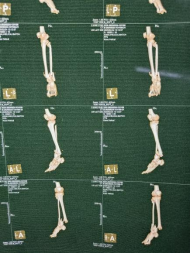

患者男性,54歲,外傷致右側(cè)脛腓骨開放性骨折8小時,局部可見右側(cè)脛骨骨折近端露出,小腿部肌肉部分損傷外露,皮膚損傷,脛神經(jīng)損傷。CT顯示右側(cè)脛腓骨遠端粉碎骨折,累及關(guān)節(jié)面,骨折斷端分離移位,成角移位。